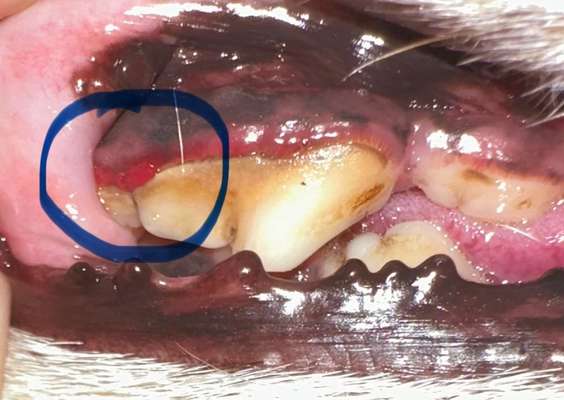

Was könnte das sein ?

Höchstwahrscheinlich eine Zahnfleisch Entzündung (Gingivitis) verursacht durch Plaque, Belag, Zahnstein und Konkremente

Unbedingt mit der Zahnpflege beginnen oder regelmäßig eine Zahnreinigung durchführen lassen

Schlechte Zähne oder Entzündungen im Mund können die Ursache für innere Erkrankungen werden wie z.B. Herzprobleme

Die Konkremente - der schwarze Strich ganz oben Zahnfleisch entlang kriegst du selbst nicht mehr weg. Das müsste unter Narkose mit einem scaler oder kürette entfernt werden.

Auf jeden Fall zum Tierarzt, das sieht schon stark entzündet aus, das ist auch Schmerzhaft für den Hund, vielleicht brauchst dein Hund Antibiotika, wird der Tierarzt dir sagen können und danach würde ich eine Zahnreinigung unter Narkose machen lassen.

Ab zum TA (nach den Feiertagen), starke Zahnfleischentzündungen wie diese können zu Herzproblemen durch Bakterien, die in die Blutbahn gelangen führen.